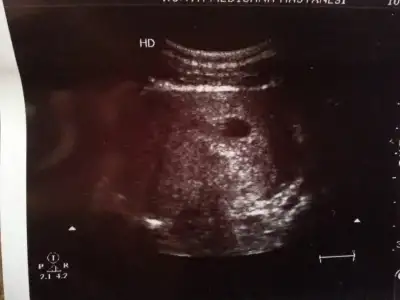

benim kız diyorr ama ben inanmıyorumm benim içime hep oğlan doğuyorrr